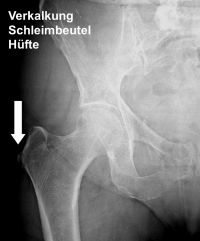

Sichtbar ist eine schmerzhafte Verkalkung der Schleimbeutel am Hüftgelenk. © Gelenk-Klinik

So können beispielsweise MRT (Magnetresonanztomografie) und Ultraschall einen entzündeten Schleimbeutel darstellen. Ein Röntgenbild zeigt, wenn sich in einem Schleimbeutel bereits Verkalkungen gebildet haben. Zudem kann eine Blutuntersuchung Hinweise auf eine bakterielle Infektion geben, die möglicherweise verantwortlich für die Schleimbeutelentzündung ist.